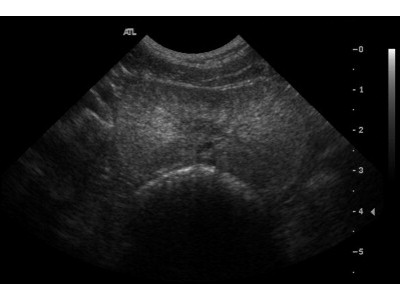

Our mini-series continues this week by discussing a topic concerning ‘man’s best friend’ – the dog. A common ailment afflicting the older members of the canine generation is a condition called Benign Prostatic Hyperplasia (BPH). To better understand this condition we need to be familiar with the role and function of the prostate itself.